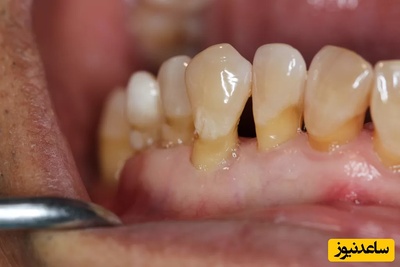

عفونت دندان با دندان درد آغاز می شود. اگر دندان پوسیده و آسیب دیده بدون یک اقدام درمانی مناسب رها شود دندان دچار عفونت می شود. همچنین عفونت دندان درمان نشده می تواند به تمام نقاط بدن سرایت کند. این عارضه دردناک معمولا ناگهانی بروز نمی کند و بر اثر عدم درمان و رسیدگی به پوسیدگی های دندانی و بیماری های لثه در طی طولانی مدت بروز می کند.در صورتیکه پوسیدگی دندان زیاد باشد به مرور زمان عصب مرکزی دندان درگیر می شود و اگر بیمار تحت درمان عصب کشی قرار نگیرد دندان عفونی می شود و در ناحیه ریشه دندان در داخل استخوان فک کیست Cyct تشکیل می شود در بعضی موارد کیست ایجاد شده به داخل دهان سرباز می نماید و عفونت ایجاد شد خارج می شود و بیمار با آبسه دندانی و عفونت و درد به مطب دندانپزشکی مراجعه می نماید درمان این عارضه در صورتی که کیست کوچک باشد. عصب کشی یا Root canal therapy است و در صورتی که کیست بزرگ باشد باید با جراحی کوچکی که در مطب انجام می شود کیست ناحیه انتهای ریشه را برداشت. بدین صورت که بر روی لثه بیمار برشی با تیغ بیستوری داده می شود و به انتهای ریشه دندان دسترسی ایجاد می شود و با جراحی باز کل ناحیه عفونت خارج می گردد و ناحیه با سرم فیزیولوژی شسته می شود وانتهای ریشه با مواد پرکردگی پر می شود و دوباره لثه بر روی استخوان بخیه زده می شود.

- ورم شديد در داخل يا خارج دهان در محل لثه در اطراف يک يا چند دندان يا بر روي صورت. اين ورم ممکن است همراه با درد يا بالا رفتن دماي بدن باشد و يا بدون اين علائم باشد.

- پيدايش ورم يا يک برآمدگي بسيار کوچک بر روي لثه در قسمت بالا يا زير دندان که ممکن است دردناک يا بدون درد باشد. همچنين ممکن است يک مزه خاص و غير طبيعي در دهان خود احساس کنيد.